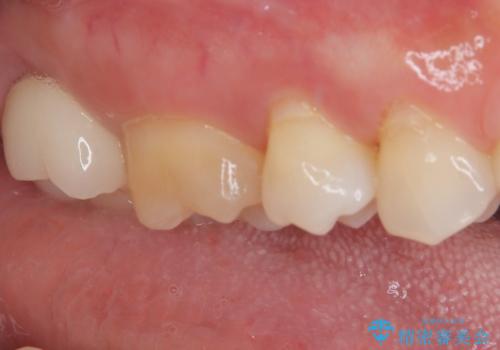

食事をすると痛む奥歯 オールセラミッククラウンでのむし歯治療

- 上顎大臼歯が食事の度に痛みを感じるとのことで来院された患者様です。

レントゲン写真などで診査を行ったところ、神経組織が壊死し、根尖部周辺の骨に炎症が認められました。

まずは根管治療を行い、症状が消退したことを確認してオールセラミッククラウンにて補綴治療を行うこととしました。